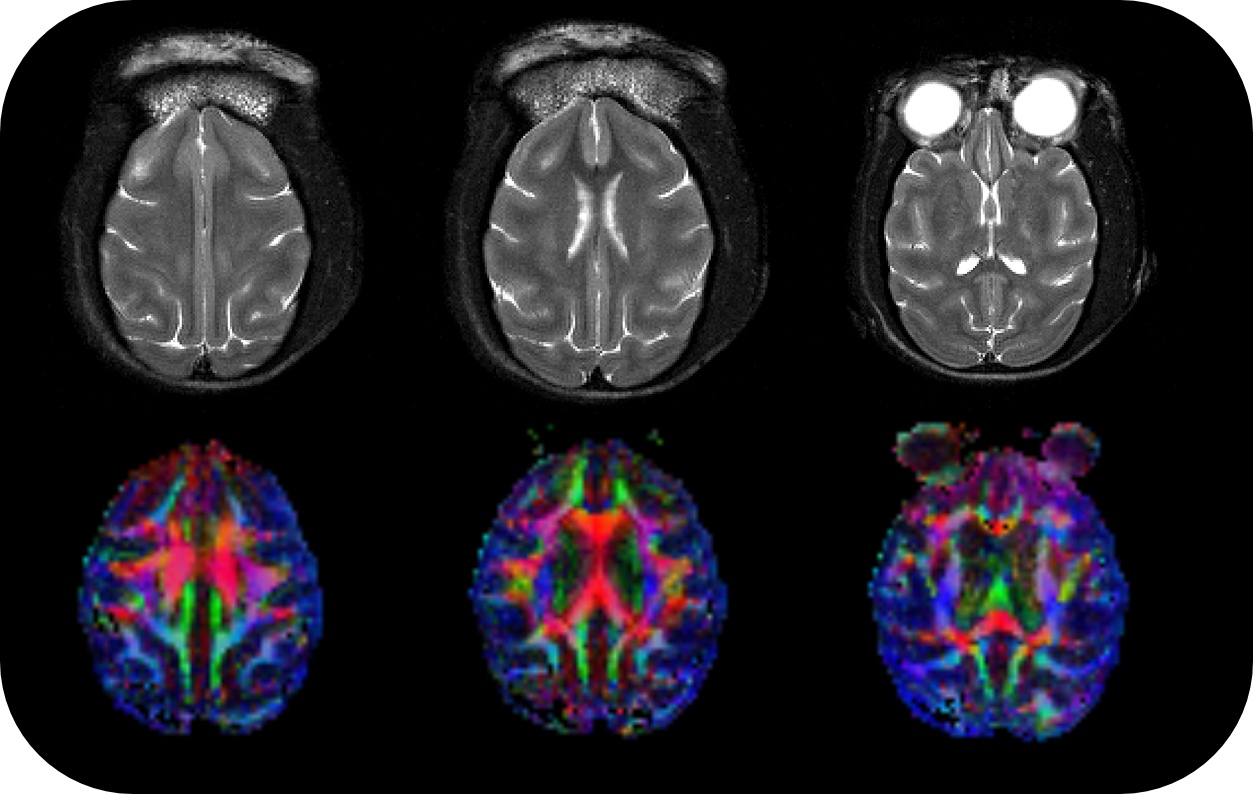

由于BioSpec 70/30的大孔径尺寸,食蟹猕猴的各向异性(FA)图可以很容易地在BioSpec上成像。图片来源:美国北卡罗来纳州温斯顿-塞勒姆,维克森林浸信会医学中心。